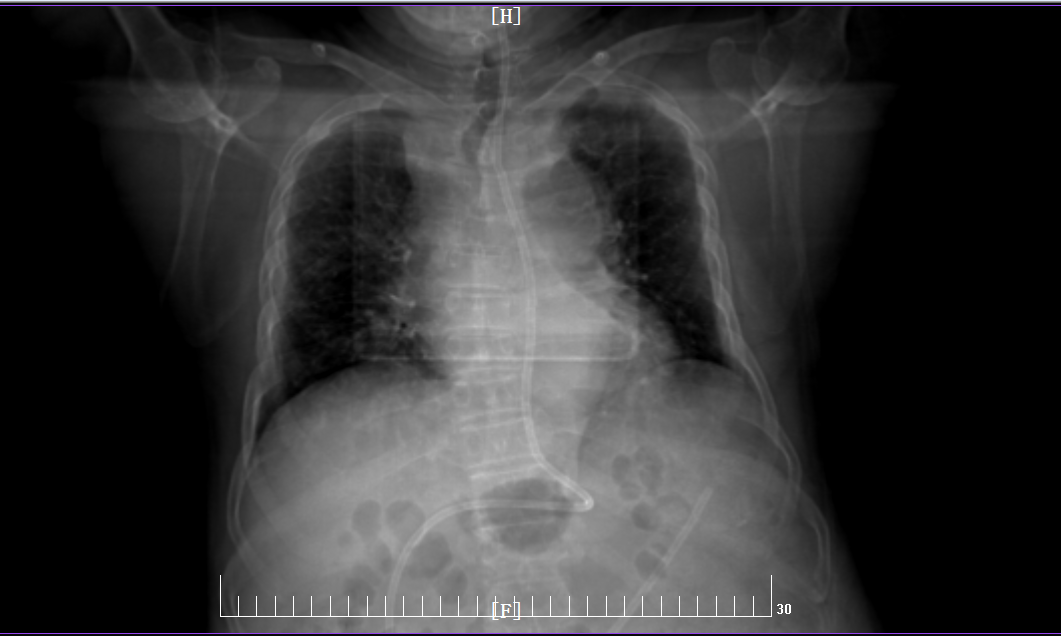

此次二一五医院引进的床旁便携式可视化引导下鼻肠管置入技术,核心优势在于置管全程可视化。操作者通过高清内窥镜,可实时清晰观察食管、胃、十二指肠的解剖结构,如同为置管操作装上“透视眼”,精准把控导管走向,一次性将鼻肠管送达十二指肠或空肠的目标位置。相较于传统盲插法,该技术有效降低鼻腔黏膜损伤、导管异位等并发症发生率,提升操作效率,缩短置管时间,减轻患者不适感;无需依赖X线定位,既规避了辐射暴露风险,也减少了危重患者转运过程中的安全隐患,真正实现了精准、快速、安全、舒适的置管目标。